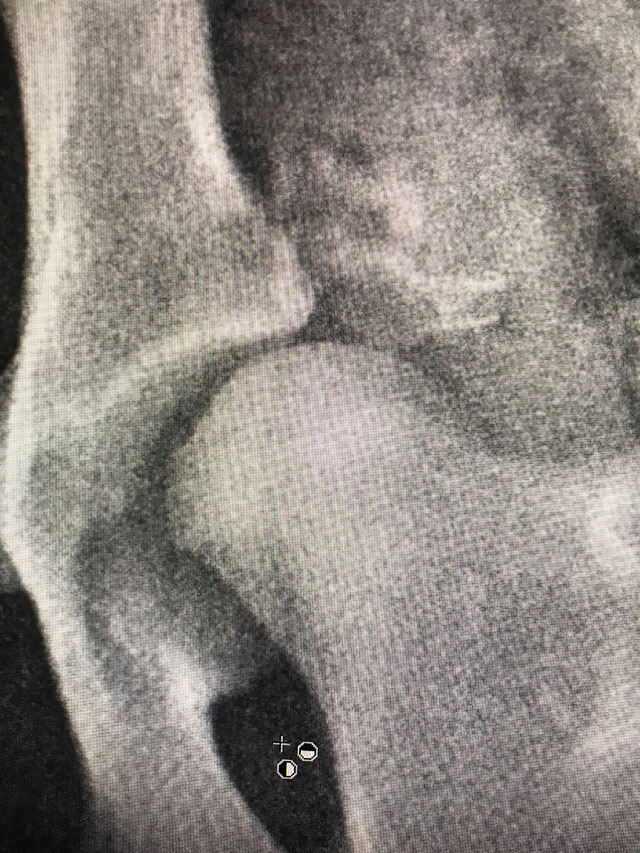

(DARthroplasty)Plastyka DAR to zabieg polegający na nadbudowie panewki stawu biodrowego z zastosowaniem autoprzeszczepu fragmentów kości pobranych najczęściej z talerza biodrowego. Operacja stanowi alternatywę dla osteotomii miednicy - zabiegu TPO/DPO - w przypadku pojawienia się zmian degeneratywnych w stawie lub zaawansowania wieku/masy pacjenta. Technika mocowania przeszczepów kostnych do krawędzi panewki stawu i ich wzajemnego ułożenia jest kluczowa dla powodzenia zabiegu.

Operacja plastyki DAR jest zabiegiem mniej agresywnym i mniej restrykcyjnym od osteotomii TPO/DPO i może być wykonywany jednocześnie na obu stawach pacjenta. Operacja DAR powinna być postrzegana jako zabieg umożliwiający funkcję stawu i ograniczający cierpienie zwierzęcia, nie jest to zabieg prowadzący do trwałego wyleczenia schorzenia o charakterze genetycznym, rozwojowym.